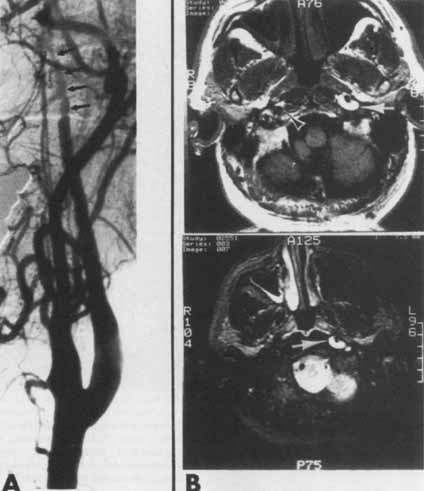

In the neck, as the sympathetic fibers ascend in relationship with the carotid sheath, oculosympathetic paresis may ba caused by enlarged lymph nodes, tumors, abscess, trauma146,147,148 and acute carotid thrombosis.149 Horner's syndrome with associated ipsilateral neck, facial, or orbital pain150 and, less frequently, amaurosis fugax, disagreeable taste (dysgeusia),151 or facial numbness and dysesthesia,152 strongly suggests spontaneous internal carotid artery dissection. Bougousslavsky et al.153 reported the presence of Horner's syndrome in 20% of their patients with spontaneous carotid dissection. Biousse et al.154 studied 146 consecutive patients with extracranial internal carotid dissection and found 52% had ophthalmic findings that were initial manifestations of dissection. Fourty-five percent of patients had painful Horner's syndrome, and this remained an isolated finding in 50% of these cases. Hydroxyamphetamine 1% provides rapid corroboration of a postganglionic (third-order neuron) level lesion, and cerebral angiography or—less invasively and perhaps preferably—cervical magnetic resonance imaging is diagnostic156,157 (Fig. 16).

Fig. 16 Arteriogram and magnetic resonance imaging (MRI) scan of two patients with left spontaneous carotid artery dissections. A. Arteriogram (lateral view, left common carotid injection) shows a tapered narrowing (black arrows) of the left internal carotid artery with slow flow. The abnormal artery segment extends from the C2 level to the base of the skull. (The patient, a 52-year-old woman, initially noted left amaurosis fugax and left upper lid ptosis as well as left eye injection. On examination, she also had facial and tongue weakness). B. (Top) T1-weighted MRI scan TR = 600, TE = 20. A bright signal, denoting blood (white arrow) surrounds a dark signal indicative of flow in the left internal carotid artery. The normal right internal carotid artery is also shown as a flow void (arrowhead). The bright signal anterior to the right carotid denotes fat, which on the T2-weighted images will be much less echo-intense. (Bottom) T2-weighted MRI scan (TR = 2500, TE = 75) shows persistence of the bright signal generated by blood (white arrow) surrounding the left internal carotid artery. The fat density anterior to the right carotid artery, which was bright on the T1-weighted image, has practically disappeared on the T2-weighted scan. (The patient, a 53-year-old man, noted an acute onset, left-sided headache followed by speech and swallowing difficulties. Examination also revealed multiple left cranial neuropathies). Arteriogram and MRI scan courtesy of Richard Latchaw, MD.